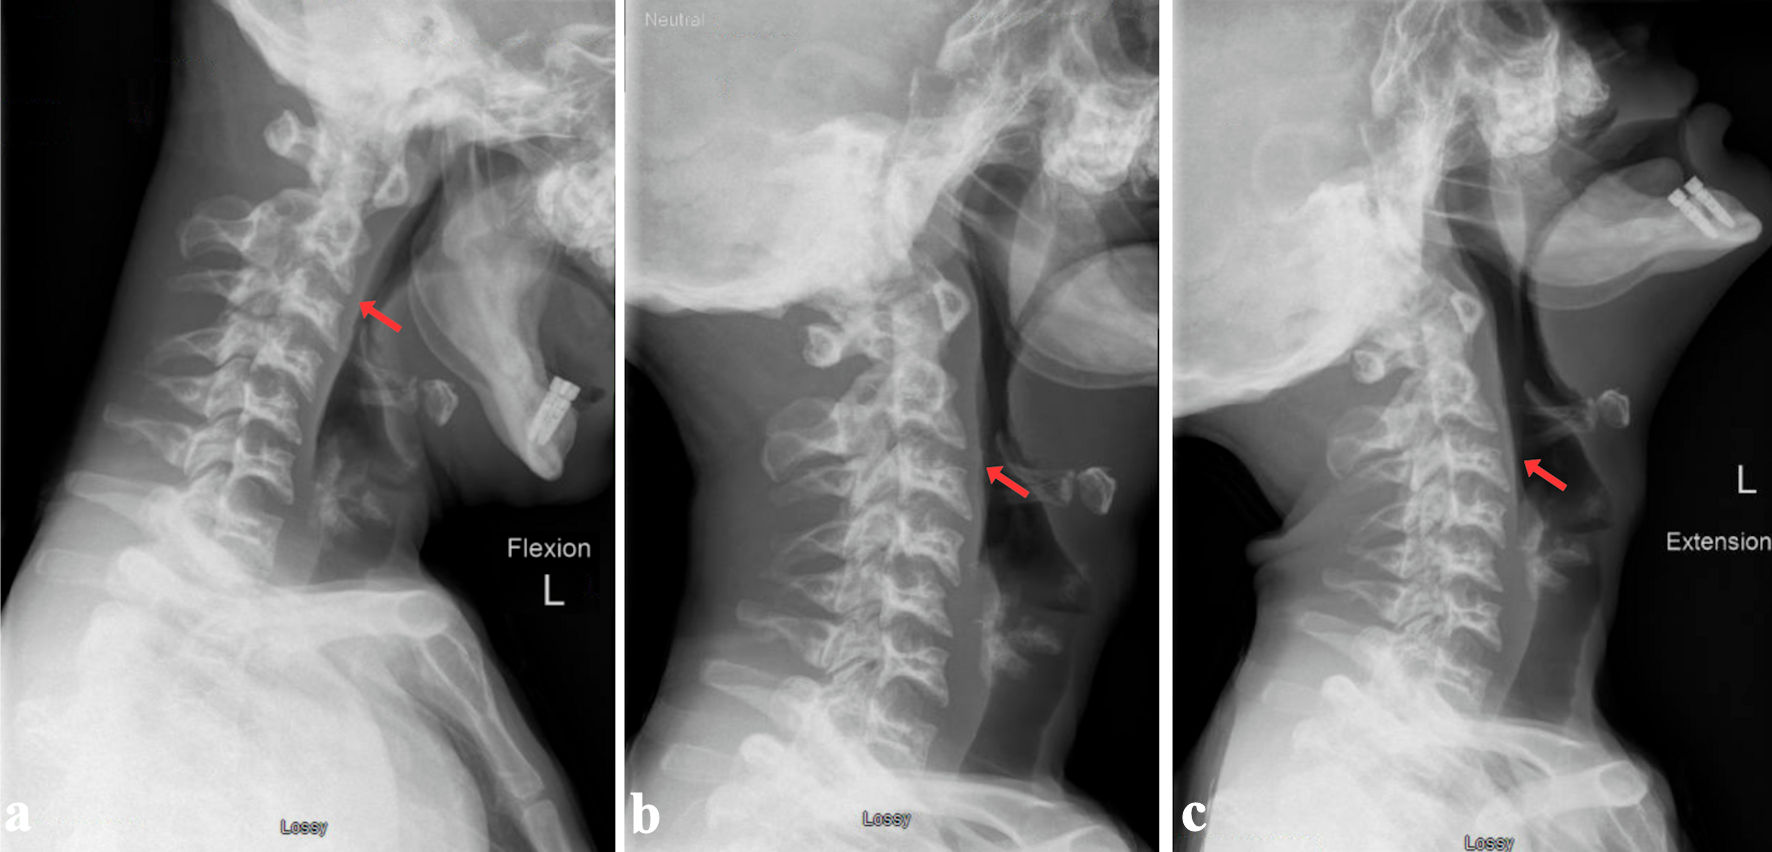

At a follow-up approximately 3 months post-injury, he remained asymptomatic with stable cervical alignment. A final dynamic flexion-extension CT of the cervical spine performed 1 year post-injury showed interval healing, with complete bone fusion of the C3 and C4 body fractures but incomplete fusion of the C4 facet and lamina (Figs. 3, 4). Alignment was stable in flexion and in extension. At his final clinical assessment, the patient remained pain-free, maintained full neurological function, and was subsequently discharged from routine neurosurgical care.

Figure 3. Radiographic follow-up at 1 year showing flexion (a), neutral (b) and extension (c) positions with no dynamic instability (red arrows).